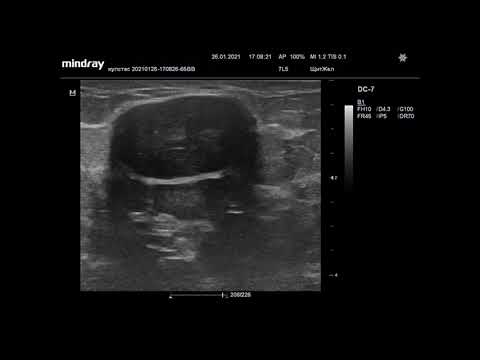

Ультразвуковая диагностика. Доктор Иогансен. Видеопримеры. Выпуск 27. Фиброаденома молочной железы.